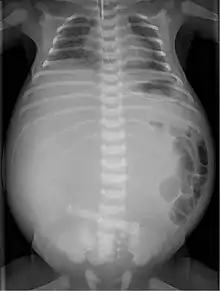

Radiograph with double bubble sign indicating duodenal atresia | |

If not diagnosed in utero, infants with intestinal atresia are typically diagnosed at day 1 or day 2 after presenting with eating problems, vomiting, and/or failure to have a bowel movement.[3] Diagnosis can be confirmed with an X-ray, and typically followed with an upper gastrointestinal series, lower gastrointestinal series, and ultrasound.[5][3]